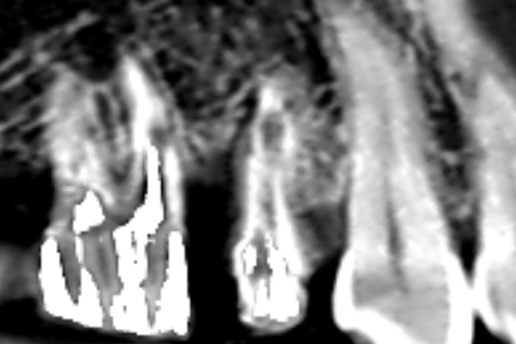

過去の根管治療が再発し再感染したケース。当院で再根管治療を実施し、歯を残した。